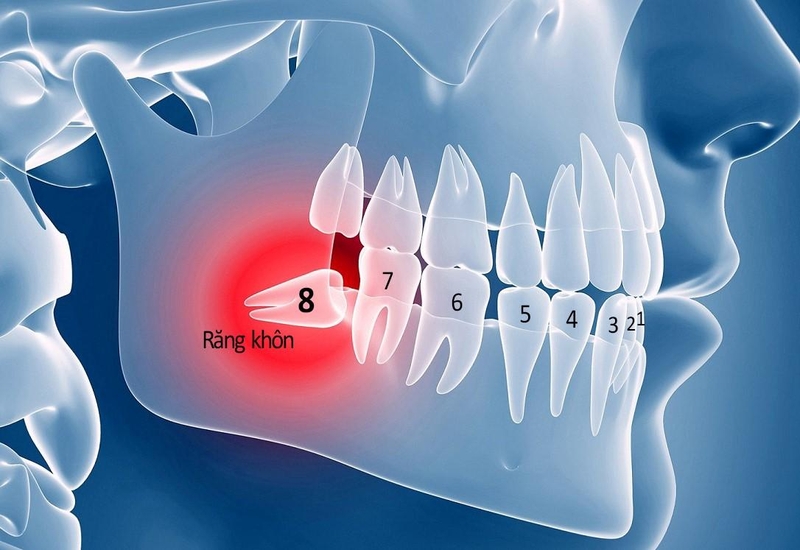

Răng khôn là tên gọi dùng để chỉ những chiếc răng mọc cuối cùng của mỗi bên hàm, hay còn gọi là răng số 8. Chiếc răng này không xuất hiện ở trẻ nhỏ khi mới mọc răng hay khi đã thay răng mà xuất hiện muộn nhất, thường ở độ tuổi trưởng thành từ 18 tuổi trở lên.

Nhổ 2 răng khôn cùng lúc có nguy hiểm không? 1 Răng khôn có thể mọc ở nhiều tư thế khác nhau gây ảnh hưởng đến răng lân cận

Thông thường, một người trưởng thành sẽ có 32 chiếc răng, trong đó có 8 răng cửa, 4 răng nanh, 8 răng hàm nhỏ, 8 răng hàm lớn và 4 răng khôn. Tuy nhiên tùy thuộc vào cơ địa mỗi người mà có người không mọc răng khôn, có người mọc 1, 2 hoặc 3 chiếc răng khôn.

Răng khôn có thể mọc bình thường như một chiếc răng vĩnh viễn, hoặc nhú lên khỏi lợi một phần thì ngừng, cũng có nhiều trường hợp răng bị kẹt trong xương hàm dẫn đến mọc ngầm và thường có xu hướng xô lệch vào răng bên cạnh.